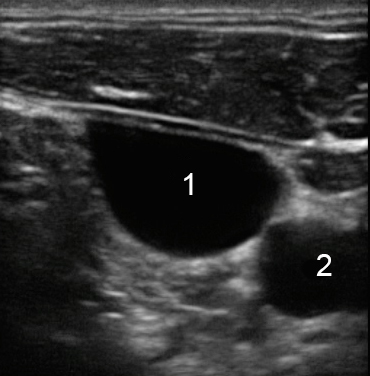

Imagen de la vena yugular interna

Vena yugular

Arteria carótida